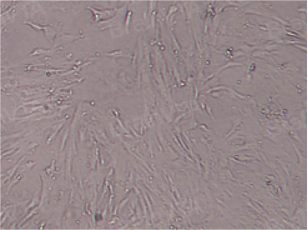

脐带间充质干细胞(P3代)

1. 细胞形态学鉴定:贴壁,成纤维细胞类似,呈梭形、不规则三角形、多边形,呈纺锤状生长,细胞中央有卵圆形核,胞质向外伸出2⁃3个长短不同的突起,当细胞密度过大时,可看到细胞成漩涡状排列。